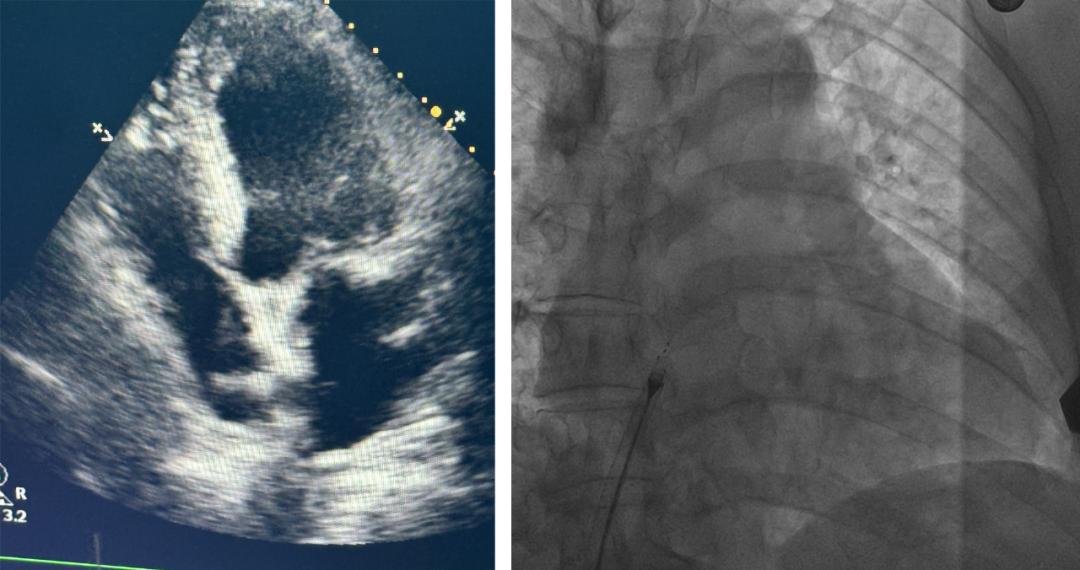

王先生入院后,主治医生武文艺及其团队立即进行了全面检查。他们综合了术前TCD发泡实验与食道彩超的检测结果,经过严格评估,最终确定其病症为卵圆孔未闭。武文艺强调,卵圆孔是胎儿心脏房间隔上的自然通道,通常在出生后数月内自然闭合。若3岁后仍未闭合,则可诊断为卵圆孔未闭。

卵圆孔未闭是先天性心脏结构的一种异常,常见于婴儿及成年后患者通常症状不明显。但王先生等少数患者会遭受如偏头痛和头晕等不适,原因不明。幸运的是,医生团队准确诊断,为王先生确定了治疗方案。

手术当天,心脏科主任张友恩博士、副主任吴三五博士、吴悠博士等医疗专家一同参与。超声科任润润医生也加入了手术团队。专家们凭借精湛的技艺和紧密的配合,为王先生成功植入了生物降解封堵器,精确地封堵了卵圆孔。